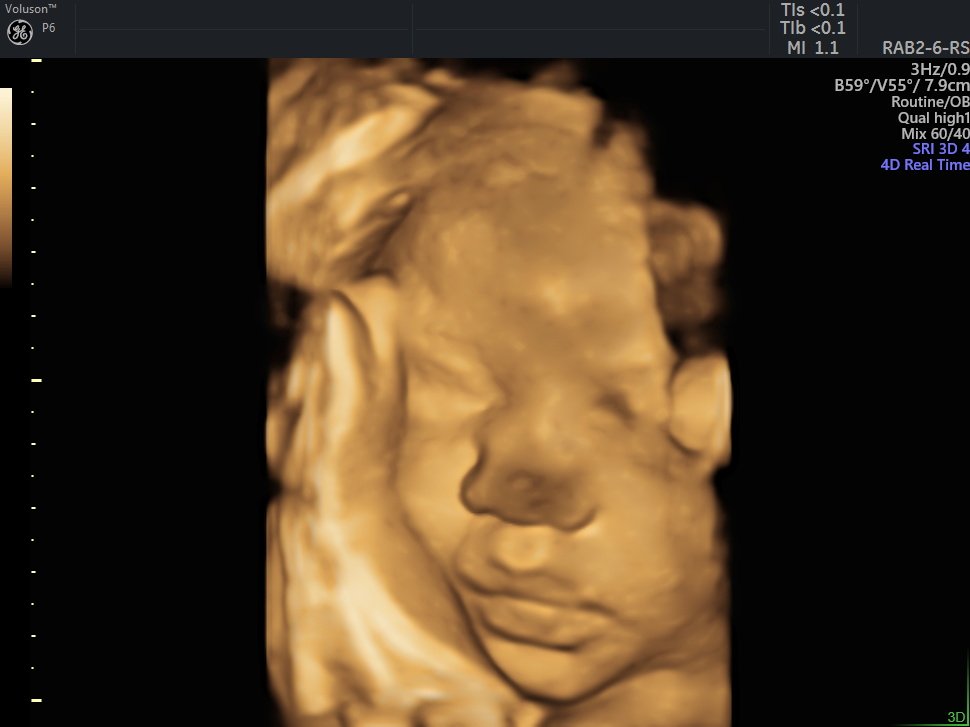

4 Boyutlu (Renkli) Ultrason ve Doppler Ultrasonografi

4 D Ultrasonografi